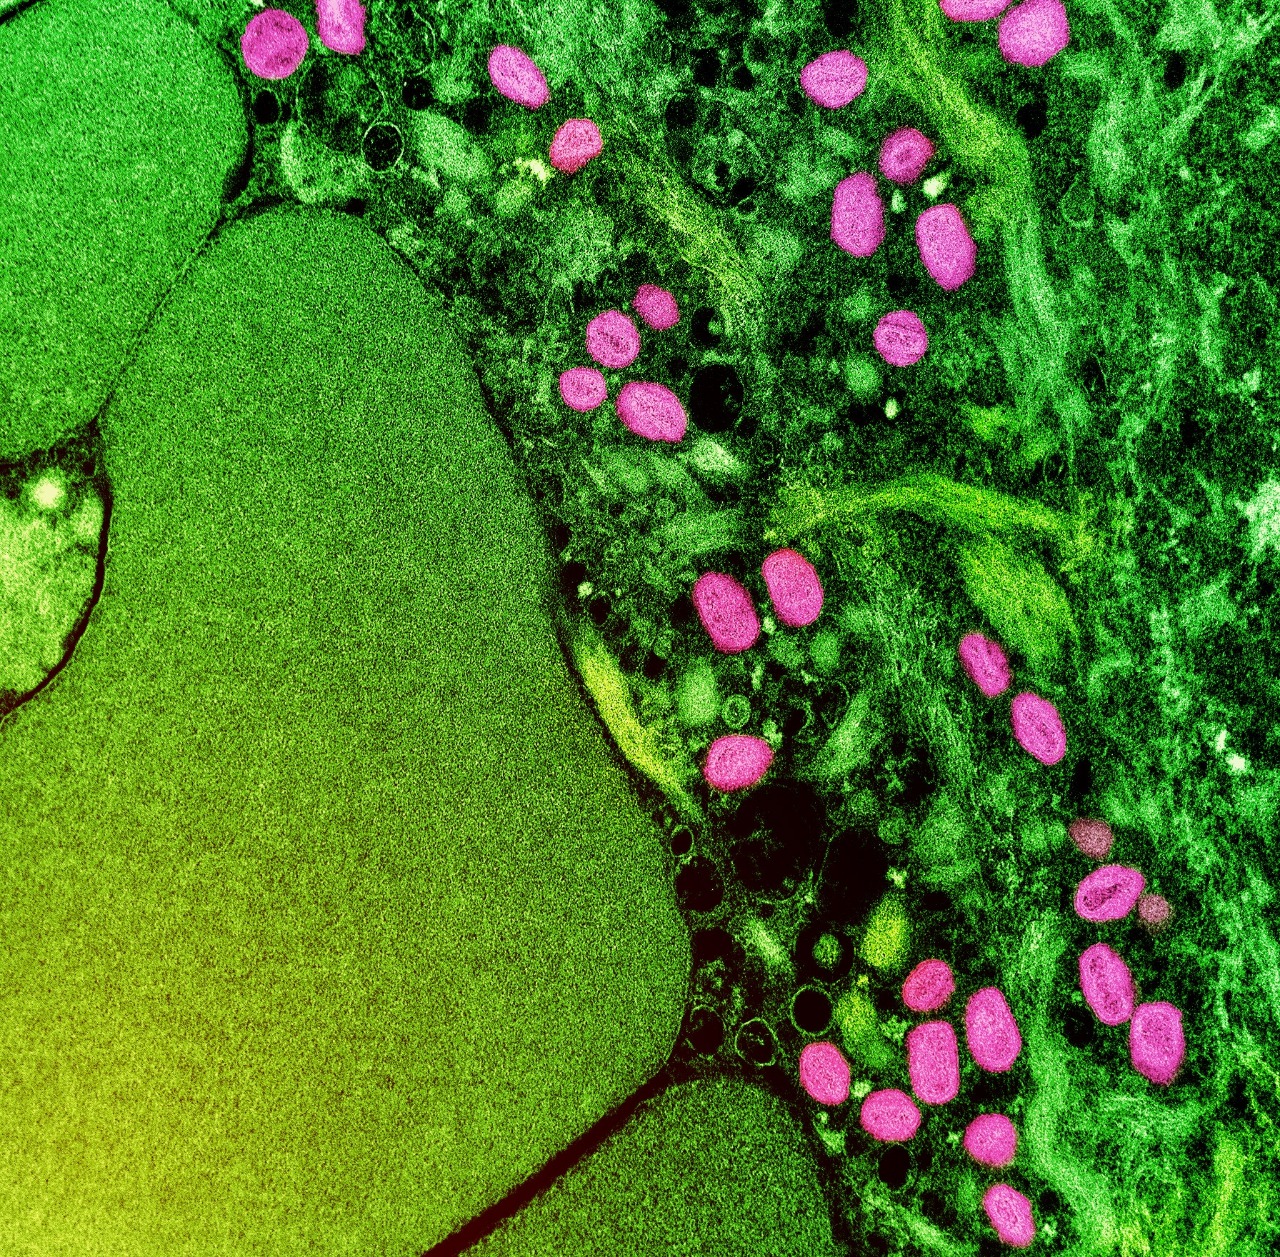

A Prefeitura de São Paulo confirmou o registro até o momento de três casos de varíola dos macacos (monkeypox) em crianças no município. São as primeiras notificações no público infantil. Conforme informou a Secretaria Municipal da Saúde, todas estão em monitoramento, sem sinais de agravamento.

Identificada pela primeira vez em macacos, a doença viral geralmente se espalha por contato próximo e ocorre principalmente na África Ocidental e Central. Raramente se espalhou para outros lugares, então essa nova onda de casos fora do continente causa preocupação. Existem duas cepas principais: a cepa do Congo, que é mais grave, com até 10% de mortalidade, e a cepa da África Ocidental, que tem uma taxa de mortalidade de cerca de 1%.

O vírus pode ser transmitido por meio do contato com lesões na pele e gotículas de uma pessoa contaminada, bem como através de objetos compartilhados, como roupas de cama e toalhas. O período de incubação da varíola dos macacos é geralmente de seis a 13 dias, mas pode variar de cinco a 21 dias.